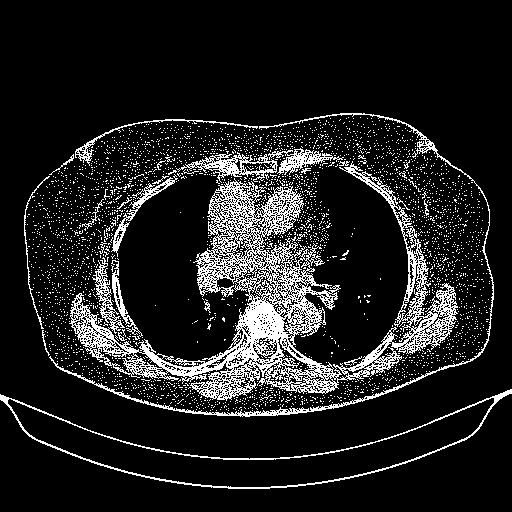

Original NATIVE CT scan (input)

Full window (WL 1023.5, WW 4095 β†’ Low βˆ’1024, High +3071)

Actual HU range: [-1024.0, 3071.0]